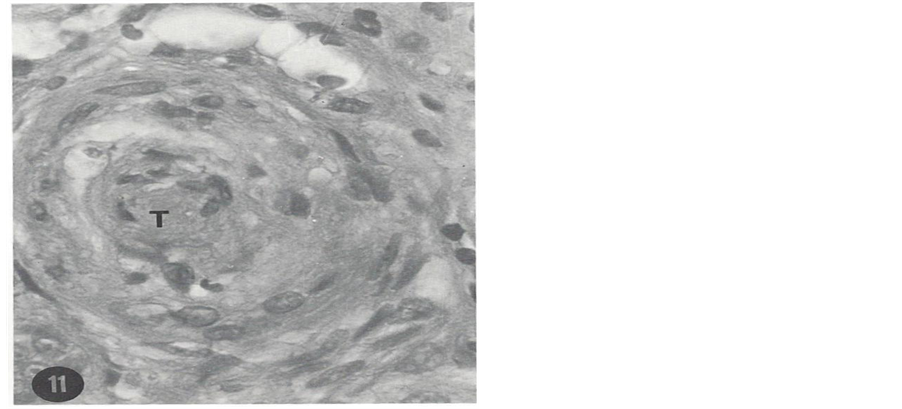

A patient is presented here to exemplify the devastating effect of uncontrolled hypertension. A 25-year-old African American male has had numerous hospital admissions in Oklahoma City, Oklahoma, USA for investigation and treatment of hypertension. He presented to a medical clinic for the first time with complaint of severe headache for four days duration in November 1972. Physical examination showed blood pressure (BP) 240/140 mmHg (stage 4 hypertension) and grade 2 (K-W-B) retinopathy. BUN and serum creatinine (ScR) were 27 mg/ dl and 2.3 mg/dL, respectively. A complete work-up for secondary hypertension including renal artery stenosis was negative. A wedge biopsy of one of the kidneys during exploratory laparotomy was obtained and studied using light microscopy (LM), immunofluorescence microscopy (IFM) and transmission electron microscopy (TEM). LM was unremarkable except for slight arteriolar thickening. IFM was negative. TEM study of an arteriole showed necrosis and hyperplasia of smooth muscle cells, small amount of collagen tissue and electron- dense deposits. These changes indicated early stage of severe vascular changes in the kidneys. He was treated with antihypertensive therapy; his BP was reduced, headache was aborted and kidney function was improved. However, he was noncompliant and not regularly taking his prescribed BP medication. Thus during routine clinic visits, his BP had always been elevated in excess of 240/140 mmHg. After 36 months he developed sudden onset of exertional dyspnea, paroxysmal nocturnal dyspnea and oliguria and was admitted into a hospital with a diagnosis of CHF. His BP was in the range of 250 - 260/140 - 150 mmHg and flame shaped hemorrhages were noted on ophthalmoscopic examination giving rise to the clinical diagnosis of malignant hypertension. His renal function was markedly decreased with BUN and Scr levels of 110 mg/dL and 11.5 mg/dL, respectively. Conservative management failed to control BP and CHF; hence he was placed on maintenance hemodialysis. Despite hemodialysis and antihypertensive therapy, his BP remained elevated. Finally in order to reduce BP, he underwent bilateral nephrectomy, after which BP could be reduced with antihypertensive therapy. He didn’t develop stroke. Kidney pathology consisted of necrotizing arteriolitis and occlusive changes which were consistent with clinical diagnosis of malignant hypertension. LM histopathology of the nephrectomy specimen is shown in Figure 1 and Figure 2.

Figure 2. Hyperplasia and necrosis of smooth muscle cells and occlusion of the lumen of a large arteriole by a thrombus (T) (H & E, 320×). From the nephrectomy specimen.